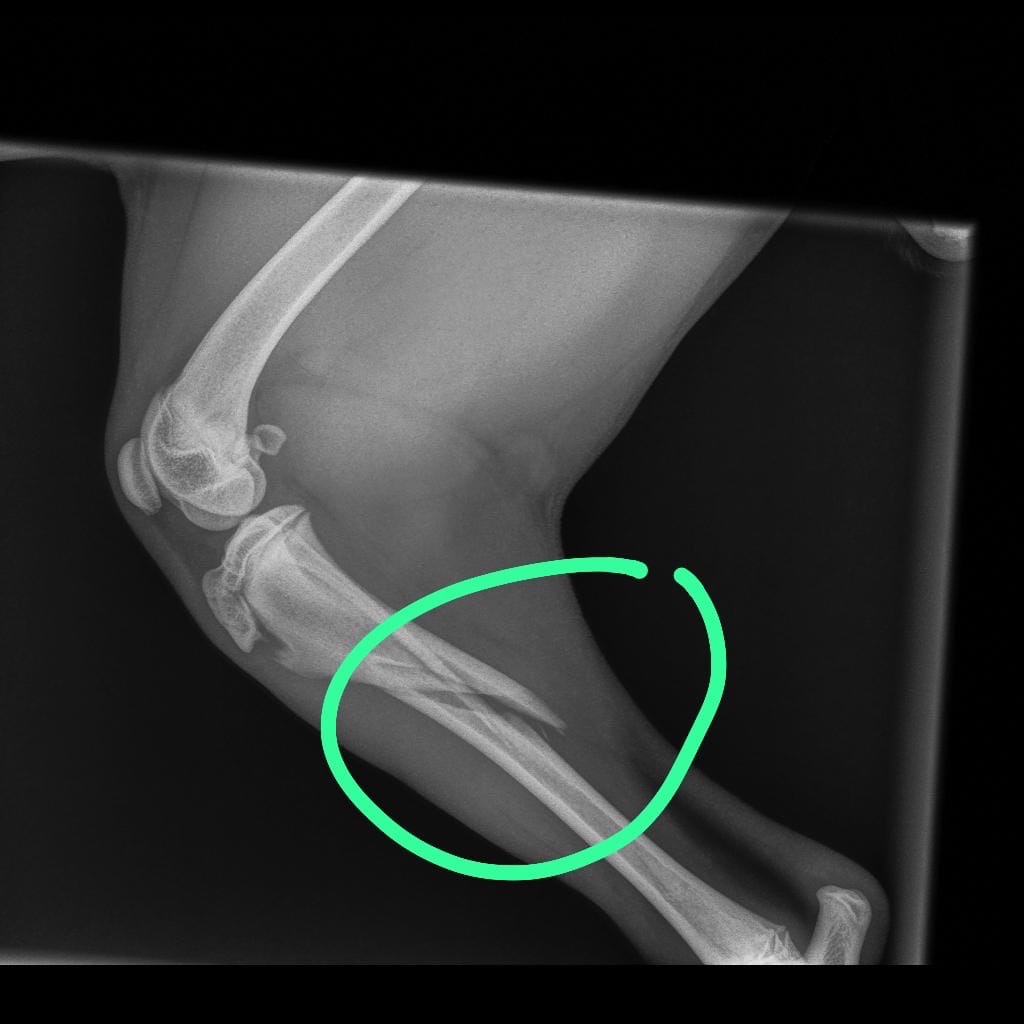

Mijn naam is percy zit in groot probleem mijn lieve hond puppy Bintang heeft ze pootje gebroken en is hoge kosten gekomen hoop dat ik hier mensen zijn die me kunnen helpen